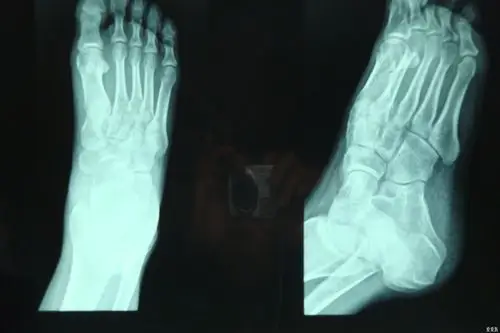

脚踝部影像